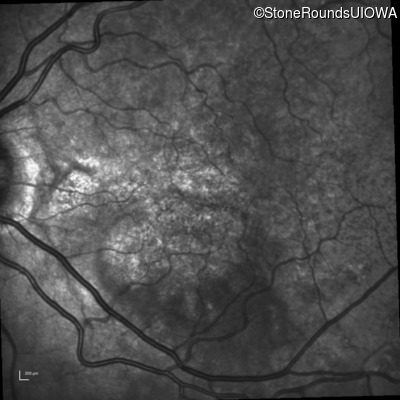

Infrared Fundus Photograph - Right - 20/20 -3 sc

Exemplar